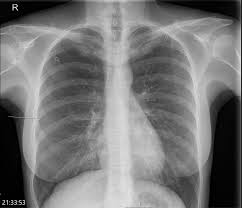

Ultrasound imaging also may be used to identify a pneumothorax. In tension pneumothorax, patients are distressed with rapid laboured respirations, cyanosis, profuse diaphoresis, and tachycardia. Keine äußere verletzung des brustkorbs. A pneumothorax occurs when air leaks into the space between your lung and chest wall. Luftaustritt aus der lunge durch die pleura visceralis. Depending on the cause of the pneumothorax, a second goal may be to prevent recurrences. A pneumothorax can be caused by: Catamenial pneumothorax is a condition of air leaking into the pleural space occurring in conjunction with menstrual periods (catamenial refers to menstruation), and or during ovulation, caused by the abnormal growth of endometrial tissue in the membrane surrounding the lung and diaphragm.

Ultrasound imaging also may be used to identify a pneumothorax.

This website is designed primarily as an educational resource. A pneumothorax can develop into a collapsed lung. Depending on the cause of the pneumothorax, a second goal may be to prevent recurrences. Patients with a pneumothorax typically report dyspnoea and chest pain. Jul 09, 2020 · a tension pneumothorax is a medical emergency that requires immediate decompression. It typically happens when there is a rupture of a small air sac on the outside of the lung. Ultrasound imaging also may be used to identify a pneumothorax. Doctors treat a pneumothorax or collapsed lung depending upon the cause. In tension pneumothorax, patients are distressed with rapid laboured respirations, cyanosis, profuse diaphoresis, and tachycardia. Consult a doctor for medical advice. Oct 09, 2019 · pneumothorax or a collapsed lung, is a lung condition in which the lung(s) has been injured by infection, trauma, disease, cigarette smoking, and other medical problems. Keine äußere verletzung des brustkorbs. Catamenial pneumothorax is a condition of air leaking into the pleural space occurring in conjunction with menstrual periods (catamenial refers to menstruation), and or during ovulation, caused by the abnormal growth of endometrial tissue in the membrane surrounding the lung and diaphragm. Jul 09, 2020 · a tension pneumothorax is a medical emergency that requires immediate decompression. It is not intended to provide medical advice on personal health matters or to guide treatment — which is only appropriately done by a qualified health professional. Luftaustritt aus der lunge durch die pleura visceralis. Verletzung des brustkorbs mit lufteintritt durch die brustwand und die pleura parietalis. It typically happens when there is a rupture of a small air sac on the outside of the lung. Tension Pneumothorax In Asthma Resuscitation Tension Pneumothorax In Asthma Resuscitation from els-jbs-prod-cdn.jbs.elsevierhealth.com